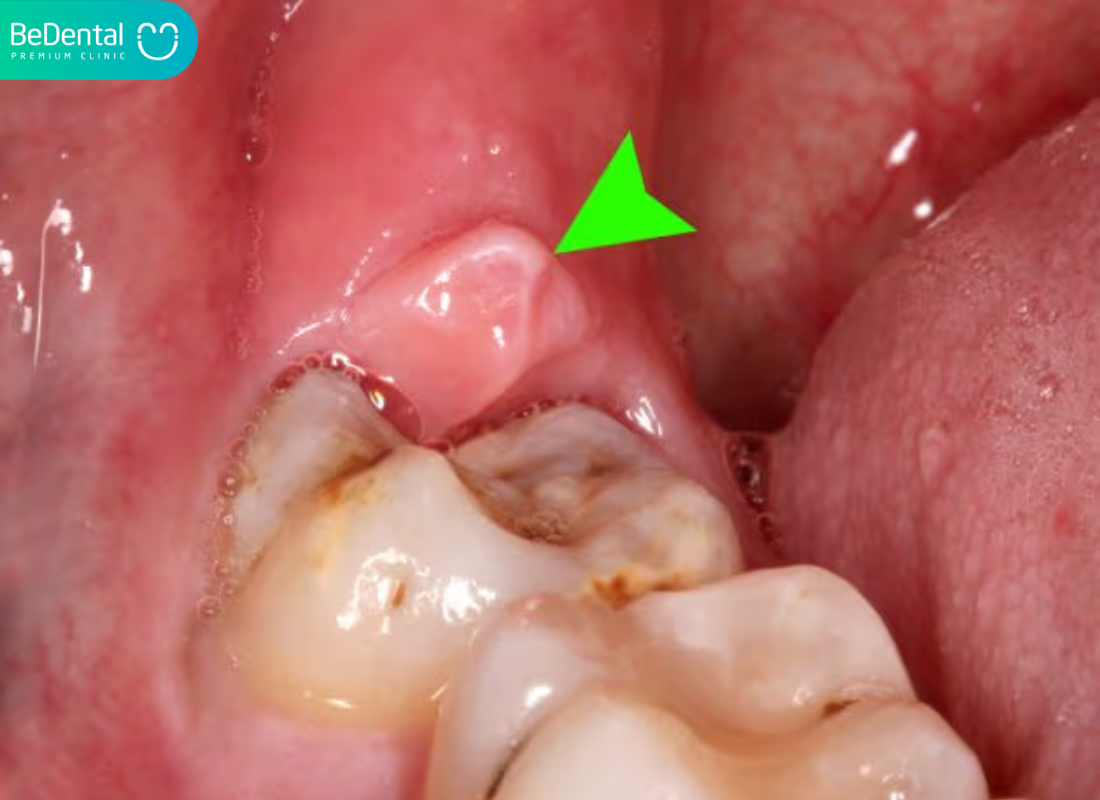

Răng và các mô nâng đỡ

Răng là thành phần cứng nhất trong Khoang Miệng, được đặt chắc chắn trong các xương ổ răng. Cấu trúc của mỗi chiếc răng bao gồm men răng, ngà răng và tủy răng chứa mạch máu, thần kinh.

Một người trưởng thành bình thường sẽ sở hữu 32 chiếc răng, được phân loại thành răng cửa, răng nanh, răng cối nhỏ và răng cối lớn để thực hiện các chức năng cắt, xé và nghiền nát thức ăn.

Bao phủ xung quanh chân răng là hệ thống nướu (lợi). Nướu khỏe mạnh thường có màu hồng nhạt, bám chắc vào cổ răng để ngăn chặn vi khuẩn xâm nhập xuống vùng xương ổ răng bên dưới. Niêm mạc xương ổ răng thường mỏng và có màu đỏ sậm hơn so với nướu chính thức, có khả năng di động nhẹ để thích nghi với các cử động của hàm.